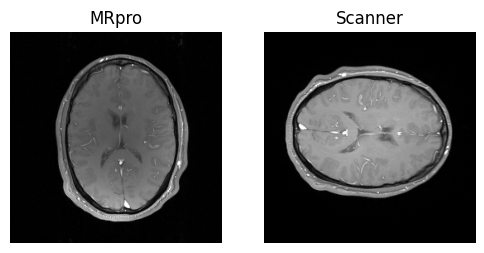

show_images(idat_pe_pf.rss().squeeze(), idat_us.rss().squeeze(), titles=['PE & PF', 'Undersampled'])

../_images/d237da143177310653ed25577e9849c1ab994d0aceaf8a083e44f5924e69c87c.png

show_images(idat_us_sense.rss().squeeze(), torch.fliplr(idat_dcm.rss().squeeze()), titles=['MRpro', 'Scanner'])

../_images/795f866a1edc519d5bd33fc53cddf2e9e23e0752c4652710a027d784b3ad9749.png

The MRpro reconstruction shows some residual intensity variations due to the multi-coil acquisition. For the vendor reconstruction this has been compensated for by using an additional scan with the body coil. This is not yet available in MRpro but all the building blocks are there to implement it. We look forward to your contribution!